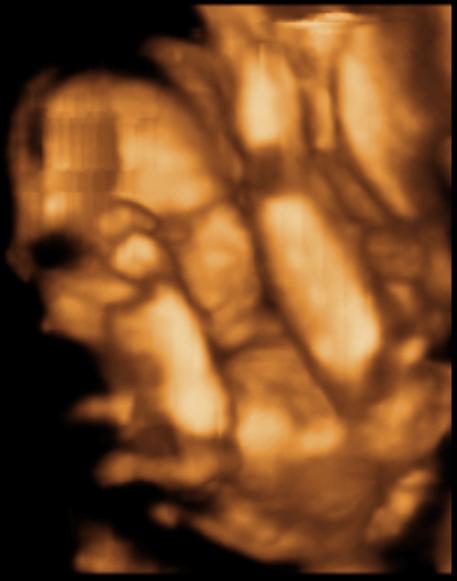

Pocaklakóm